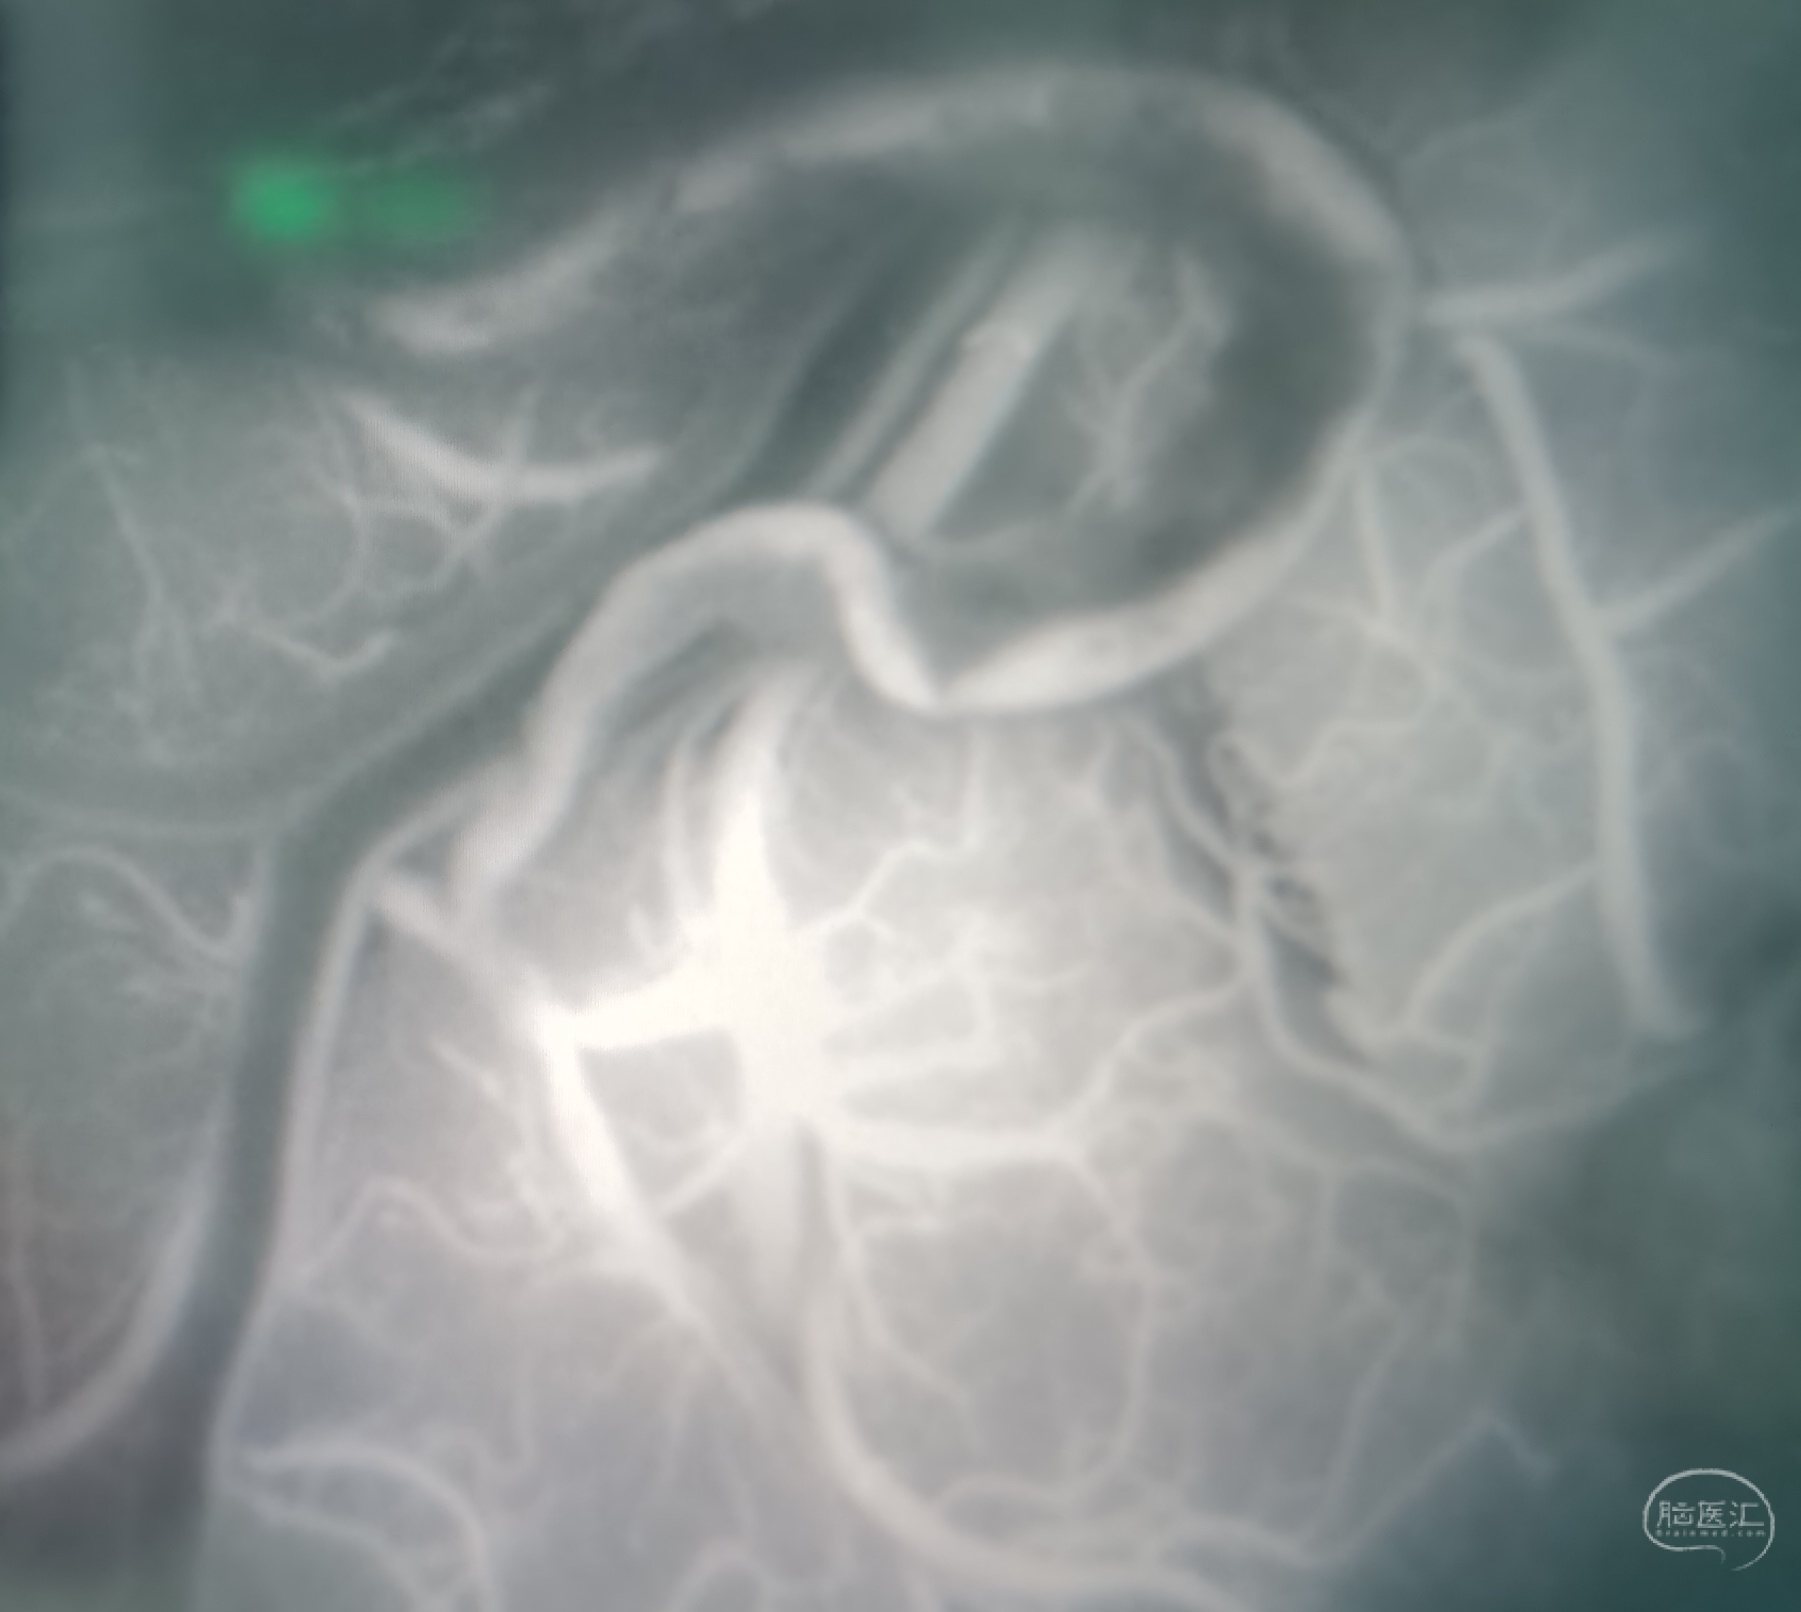

荧光造影示:吻合桥动脉通畅。

荧光造影示:吻合桥动脉通畅。

荧光造影示:吻合桥动脉通畅。

荧光造影示:吻合桥动脉通畅。

荧光造影示:吻合桥动脉通畅。